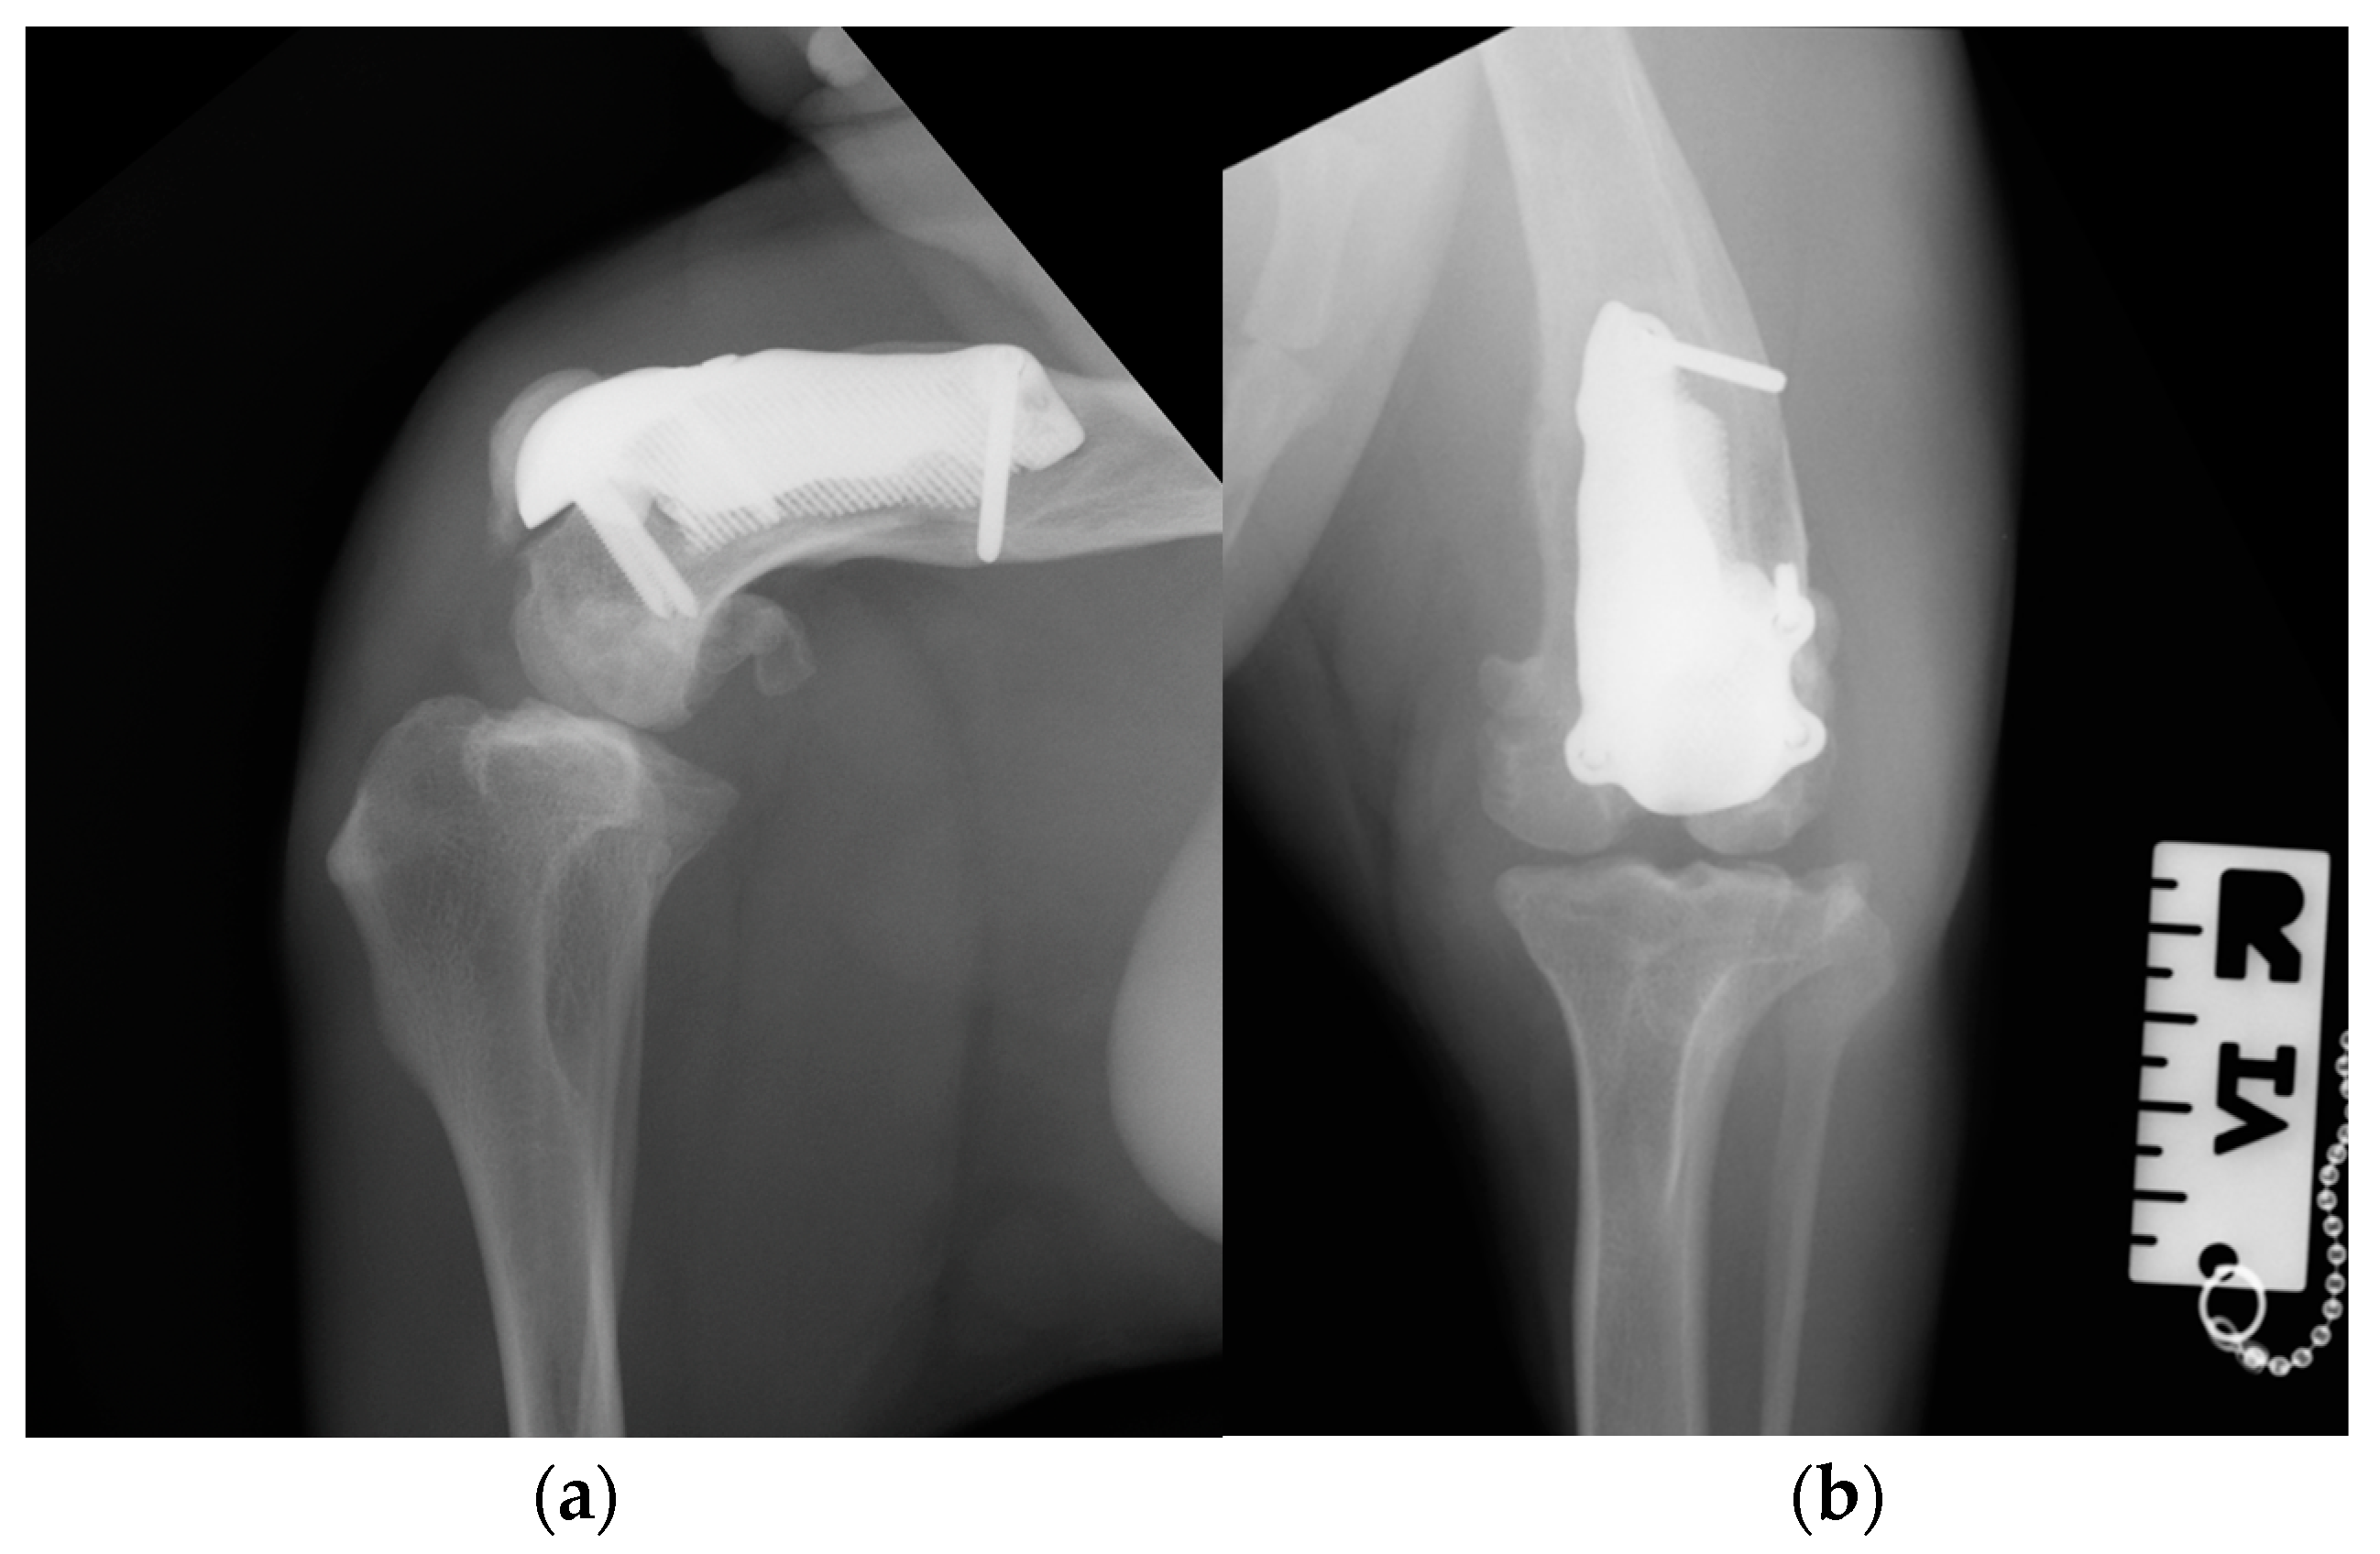

At the 6, 12 and 18-month follow-up (Video S3c), the orthopedic evaluation revealed crepitus, but a grade 0 right limb lameness, absence of patellar ligament desmitis and palpation of the right stifle joint did not elicit pain. The estimated angle of extension and flexion of the right stifle was 160-80° respectively, while the ROM of the contralateral healthy limb was 160° in extension and 40° in flexion. The thigh circumference of the pathologic limb was 40 cm compared with 47 cm of the healthy one. The radiographic images showed a good osseointegration of the implant (Figure 12).

Figure 12. Twelve-month postoperative medio-lateral (a) and caudo-cranial (b) radiographs of stifle joint showed a good osteointegration of the implant.